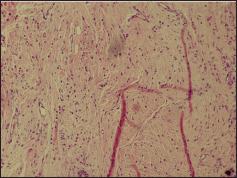

A 49-year-old pre-menopausal lady presented to her primary gynaecologist with menorrhagia of six months duration. At age 45 she had a left breast lump excision biopsy which was reported as a fibroadenoma. Clinical examination revealed a bulky cervix and uterus. A transvaginal ultrasound scan showed only fibroid uterus with endometrial polyp and minimal free fluid in the pouch of Douglas. At presentation, she had refractory bleeding requiring multiple blood transfusions. She was then taken up for prophylactic total abdominal hysterectomy and bilateral salpingo-oophrectomy. Histopathological examination revealed metastatic deposits of a lobular pattern diffusely involving the endometrium, myometrium, fibroid, cervix, and bilateral ovaries (Figure 1). The possibility of metastasis from lobular carcinoma of breast was considered. A right breast mammogram was BIRADS category 1 with no abnormal lesions. The left breast could not be mammographied because of scanty breast tissue. She presented to us with a diagnosis of metastatic lobular carcinoma involving genital tract and primary could not be detected. However, careful palpation of the scar in the left breast showed induration and two left axillary lymph nodes of size 1 × 1 cm. Fine needle aspiration from the scar revealed epithelial proliferation with cytological atypia.

Figure 1. Tumour cells infiltrating myometrium in single-file linear or Indian file pattern (H & E × 100).